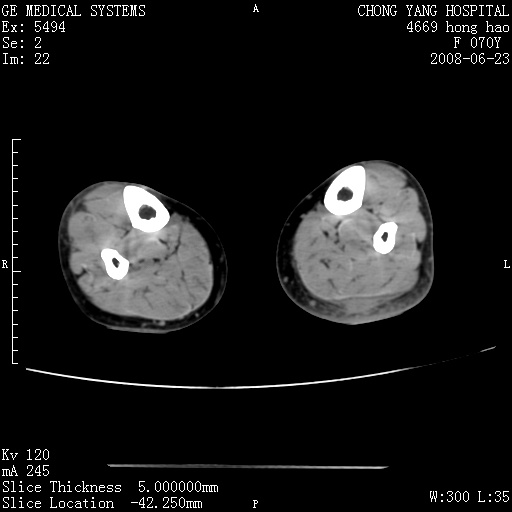

以下是引用zsl6918在2008-6-24 23:07:00的发言:[br]皮下脂肪影模糊,密度增高,但未见具体肿物影,考虑蜂窝组织炎可能性大。

以下是引用zjzjr在2008-6-24 21:44:00的发言:[br]皮下软组织肿厚,脂肪间隙混浊,考虑感染.

以下是引用peijunlong在2008-6-24 20:56:00的发言:[br]左小腿后方软组织皮下脂肪间隙见条片状密度增高影,范围较大,相邻皮下见条索影。[br]考虑:无菌性炎症可能性大[br]鉴别:主要与蔓状血管瘤鉴别,蔓状血管瘤也可表现为软组织内葡伏生长的扁平状的软组织密度影,但它的范围更大,且主要在软组织内,肌间隙中,皮下脂肪间隙内罕见。